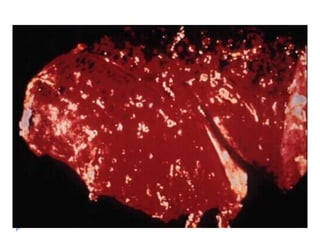

morfoloji

   Erken dönemde hemorajik, kabarık kırmızı-mavi bir

alan

   48 saat sonra soluklaĢır, hemosiderinin oluĢması ile

kırmızı- kahverengi

morfoloji  Erken dönemde hemorajik, kabarık kırmızı-mavi bir alan  48 saat sonra soluklaĢır, hemosiderinin oluĢması ile kırmızı- kahverengi  Zamanla fbröz doku periferden itibaren geliĢerek skarla iyileĢir  Histolojik olarak akut pulmoner infarkt:  Kanama alanı  Alveol duvarları, bronĢiolleri ve damarları da içeren iskemik nekroz  Ġnfark enfekte bir embolus ile oluĢmuĢsa: septik infarkt